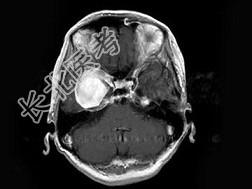

- 单项选择题女,62岁, 头痛数年,头颅MRI检查如图, 最可能的诊断是 ( )

A、脑膜瘤

B、动脉瘤

C、脑出血

D、转移瘤

E、未见异常